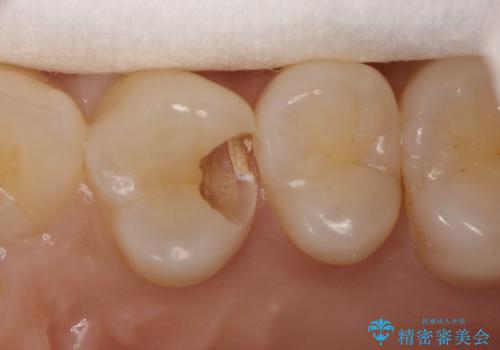

気づかないうちに大きな虫歯が 神経を保存し、セラミックで修復

- 神経を温存し、セラミックインレーによる修復をおこなった。

深い虫歯があった場合、たとえ神経を温存できたとしても長期的には痛みが出てきたり、神経がいつの間にか失活(正常な反応を失う)してしまったりするリスクはあります。

安易に神経を取り除くべきではありませんが、神経を保存するのであればそのようなリスクをよく理解していただく必要があります。